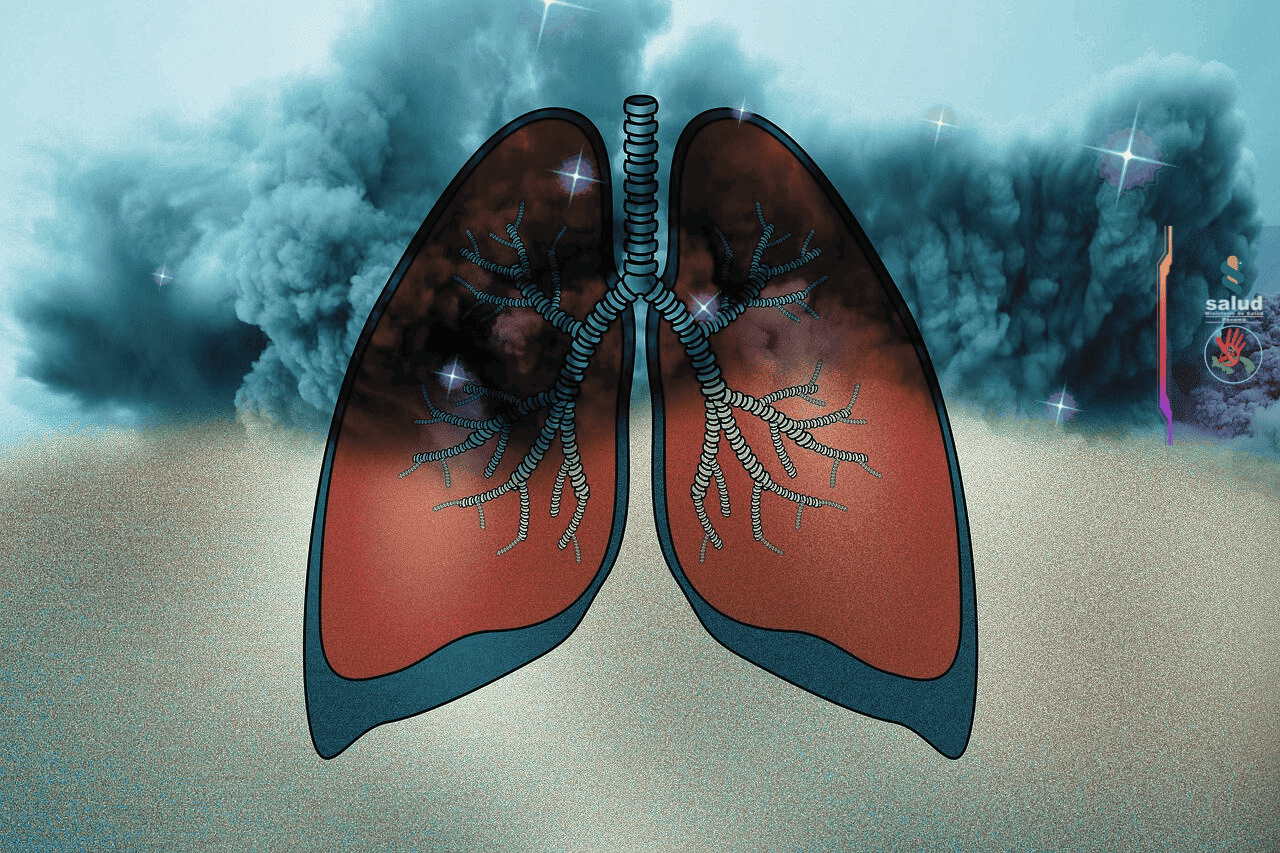

No dejes que el tabaco te quite la respiración

Pulmones de una persona que fumo por 30 años